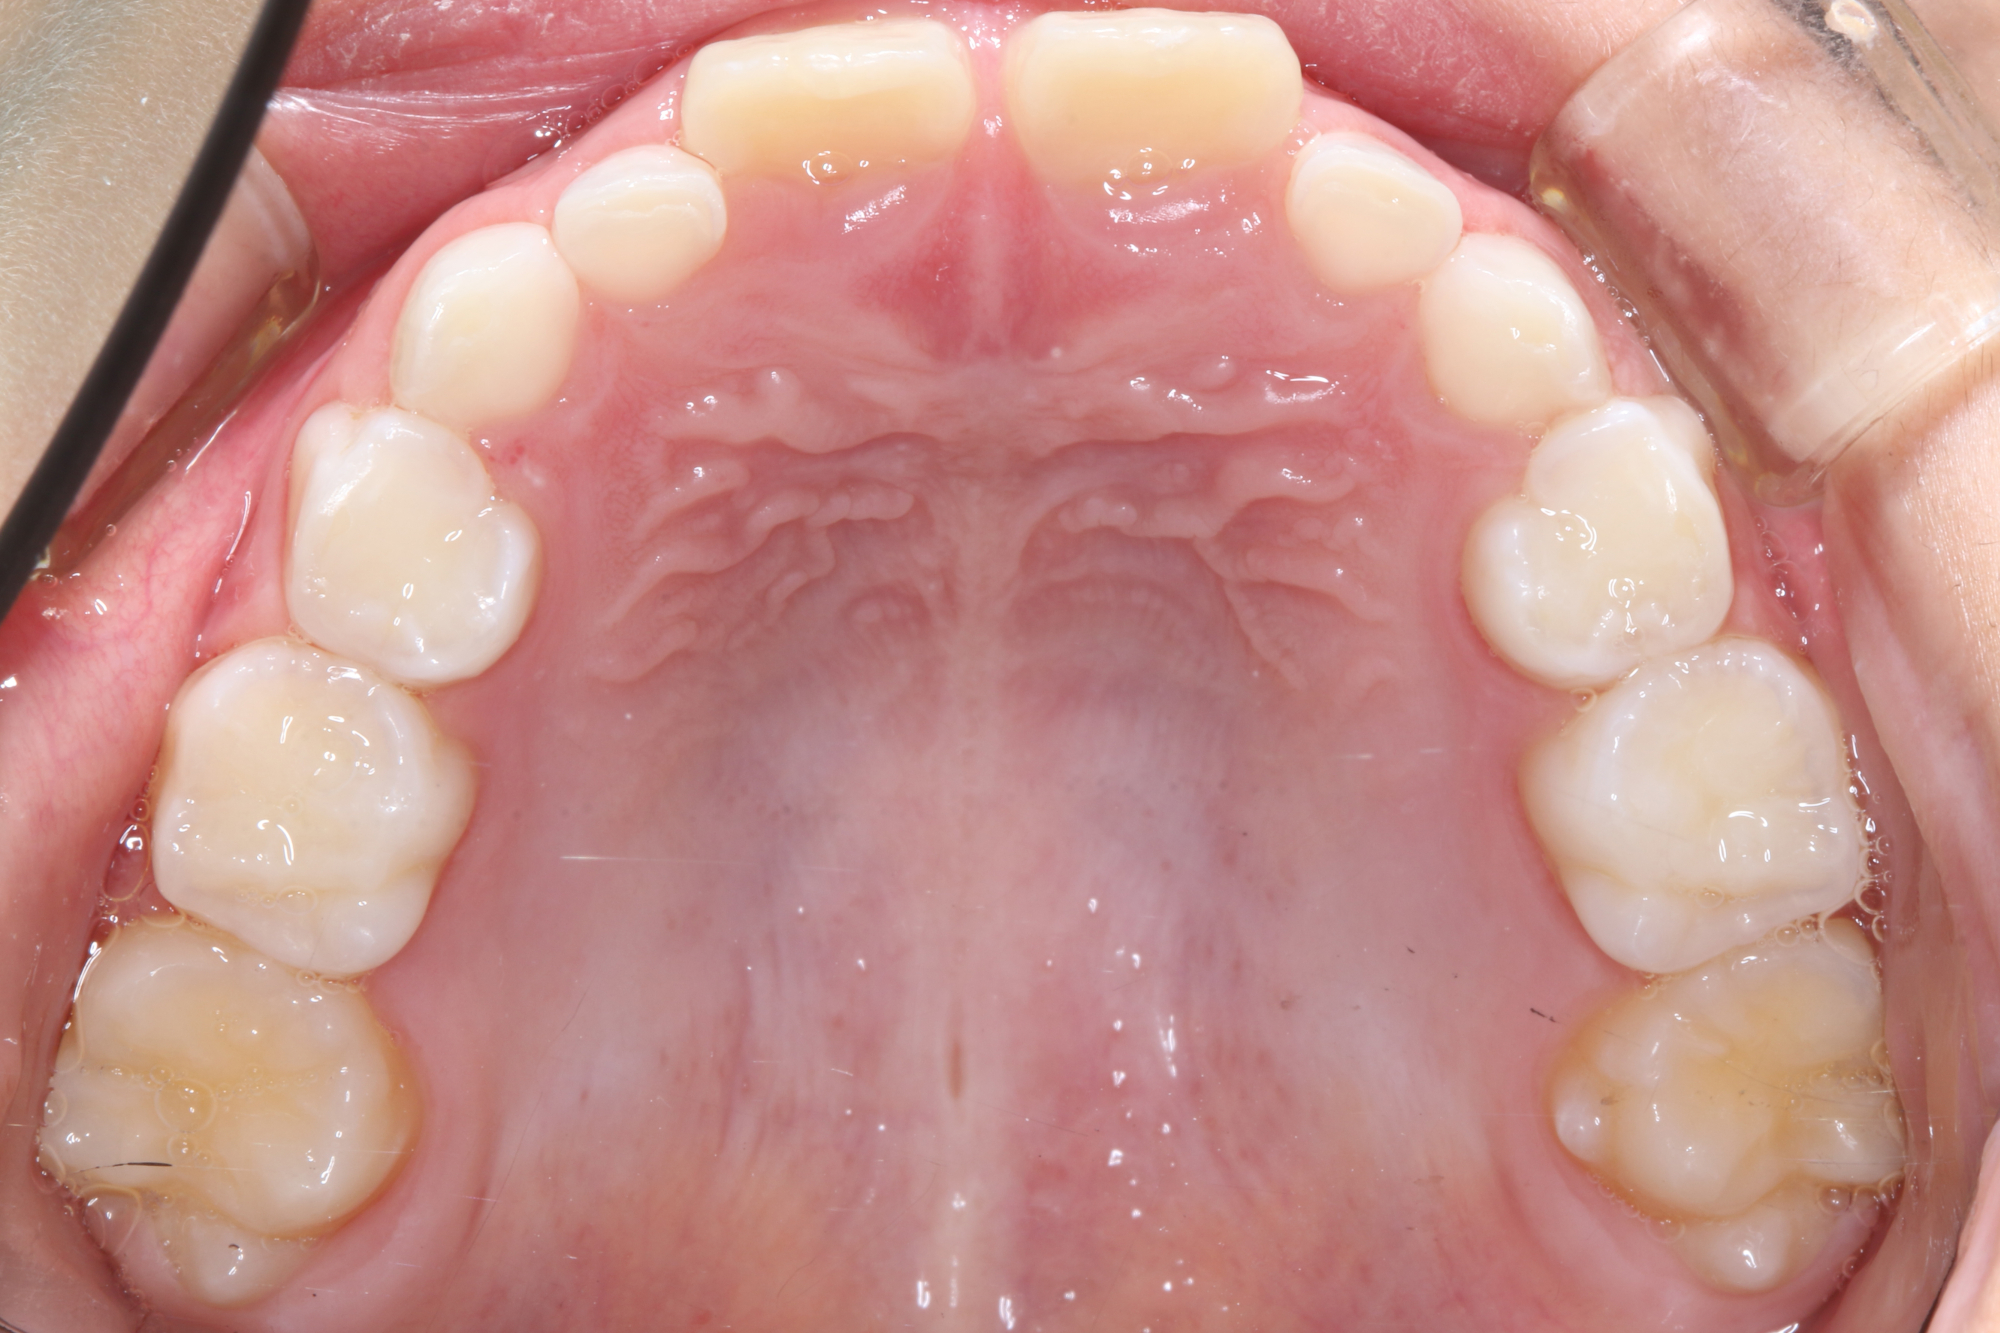

日本で行われている拡大床治療にも色々な方法がありますが当院での特長は最初に永久歯に生え替わる上下4本の前歯を奥歯の生え替わりが始まる前までに顎を拡大してきれいに並べることです。そのため拡大床治療の期間は小学校1年生頃から4、5年生頃までの間に限定しており、それまでに目的が達成できない場合には別の治療法に移行します。またゆっくりスペースを獲得するようにしているのも特長で2週間に1回ネジを回すようにしています。一般的には1週間にⅠ回ないし2回ネジを回すことが多いようです。ゆっくり進めるので一日の装着時間はお家にいるときと寝ている間だけにしています。学校や自宅以外での装着はせずゆっくり拡大していくので治療期間が長くなりますが後戻りは少なく確実になります。治療開始時期が大切ですので時期を逸した場合には拡大床治療は行いません。一般的に拡大床治療の評判が悪いのは開始時期が遅く、いつまでも治療を長引かせ治らないことによるものが多いようです。 拡大床治療はスペースを作って永久歯がならぶスペースを作ることが目標ですので細かい歯の向きや角度まで整えられないこともあります。そんな場合には別の矯正治療が必要になります。

拡大床治療ではすべての歯がきれいに並ぶように顎の成長を促すことが目的ですので細かい歯の位置や角度までは調整できません。また歯が大き過ぎる場合には口の中で歯が目立ちすぎることになる場合もあります。日本人を含めたアジア系の骨格には特長があり、ヨーロッパ系の顔立ちとは基本的に違っていますが上下の歯を抜いたりすることでそれに近づけることもできます。矯正専門の歯科ではそのような目標を立てて治療を行うことが多く、そのために4本の永久歯を抜歯することもあります。拡大床治療では歯を抜かずすべての自分の歯でしっかり噛めることを目標にしていますので口元のきれいさを目的にする治療とは異なります。歯を抜いて口元をきれいにするのは大人になってもできる治療ですので、親としては先ずはお子さんのすべての歯を使ってきれいに歯をならべることを優先すべきで、あとで本人が口元が気になるというのであれば本人の意志で歯を抜いて矯正治療を行うべきであるというのが当院の考えです。

拡大床治療は矯正治療ではありませんので完璧にきれいな歯ならびにできるわけではありません。また治療期間も長くなり期間限定の治療法ですので小学校の高学年になってから始めるのには向いていません。また拡大床治療で歯を並べる顎は拡がりますがエラの張った大きな顔になるわけではありません。歯を支える骨は歯槽骨、下顎全体は下顎骨と言って解剖学的には別の骨と考えられています。エラが張った大きな顎になるのは遺伝的な要素や咬む力が大きく影響します。拡大床治療を行ったからといって顎全体が大きくなるわけではありません。